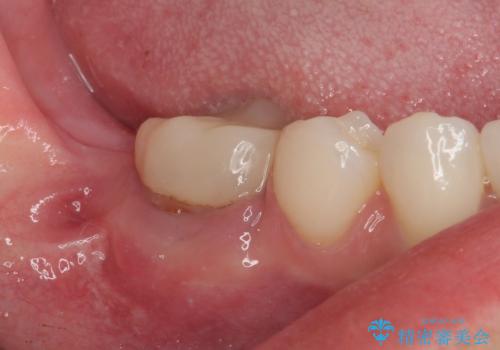

埋伏している右下第二大臼歯は、牽引して咬合に参加させることで計画しましたが、癒着などにより移動困難な場合には、抜歯の上インプラント補綴治療を行うこととしました。

右下の埋伏歯はやはり癒着しており、抜歯の後にインプラントを埋入することとなりました。

埋伏歯の牽引や、奥歯の咬み合わせ改善、インプラント補綴治療と治療期間が延びてしまう要素が多く、治療は難航しましたが、最終的に非常に満足のいく仕上がりとなりました。